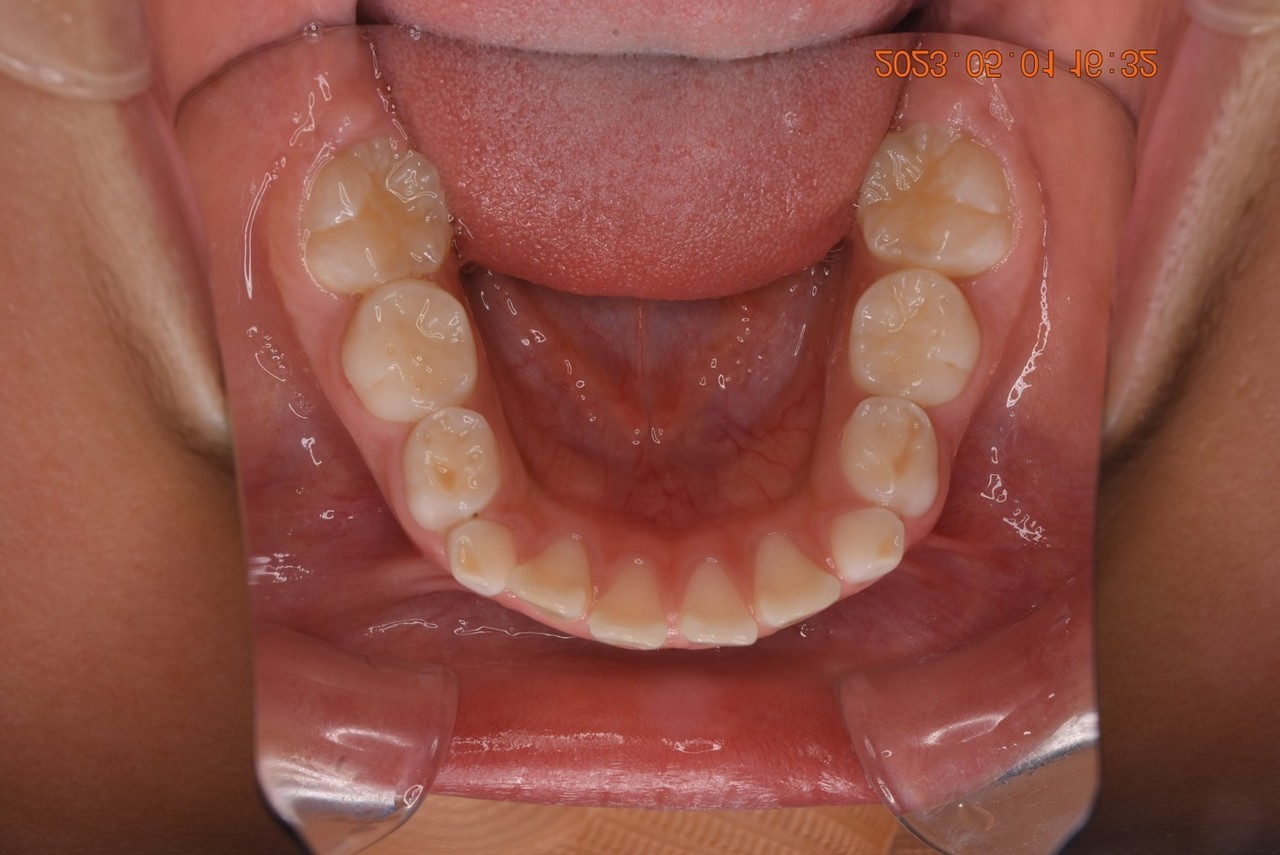

03:2番目の歯が奥に生えていた方

1期矯正治療の症例写真

1期矯正治療終了後の症例写真

第2大臼歯萌出完了

• 主訴:前から2番目の歯が後ろ側に生えている

• 診断あるいは主な症状:叢生

• 年齢:10歳(治療開始年齢)

• 治療に用いた主な装置:マルチブラケットによる歯列矯正(小児矯正)

• 抜歯部位:なし

• 治療期間:2年8ヶ月

• 治療回数:37回(矯正治療を目的とした来院)

• 治療費概算:508,000円(税込)